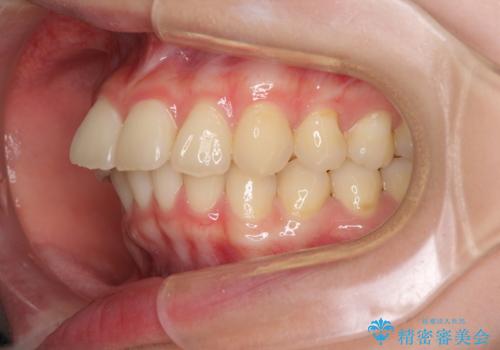

- 前歯2本が飛び出してることを気にして来院された患者様です。

全体的に黄ばんだ歯の色も気になるとのことで、マウスピース矯正により飛び出した前歯を治しつつ、ホームホワイトニングを併用して黄ばみを解消していくこととしました。

歯と歯の間を削ることで、飛び出した前歯が引っ込み、スッキリとした口元となりました。

歯の黄ばみも改善され、明るい歯並びとなりました。